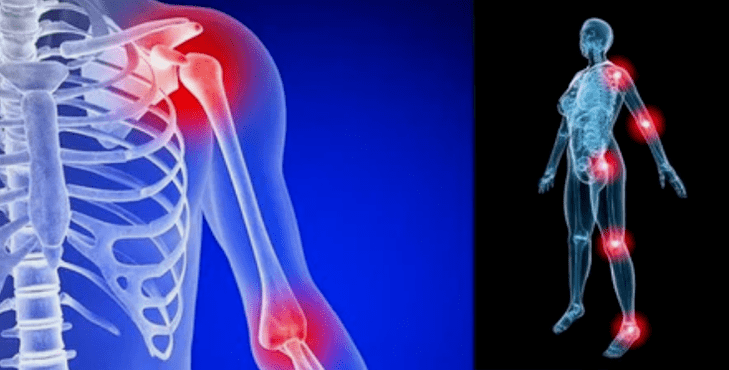

The manifestations of the disease differ little depending on the location, more often the signs are reflected on the knees, on the joints of the shoulder and hip, due to the high load.

- Pain.They have a low severity in the initial phase, with the aggravation of the state of sensation.Initially, the joints hurt only after waking up, after a hot light, the sensations disappear.Over time, the pains appear at night, they disturb considerably during and after the prolonged walk, the race, etc.At the last phase, pain syndrome pursues a person all the time;

- swelling with redness.It is located near the sick joint, this indicates an inflammatory process and a progression of the disease.The doctor understands that the synovial shell is influenced, this causes the accumulation of fluid and an increase in pain;